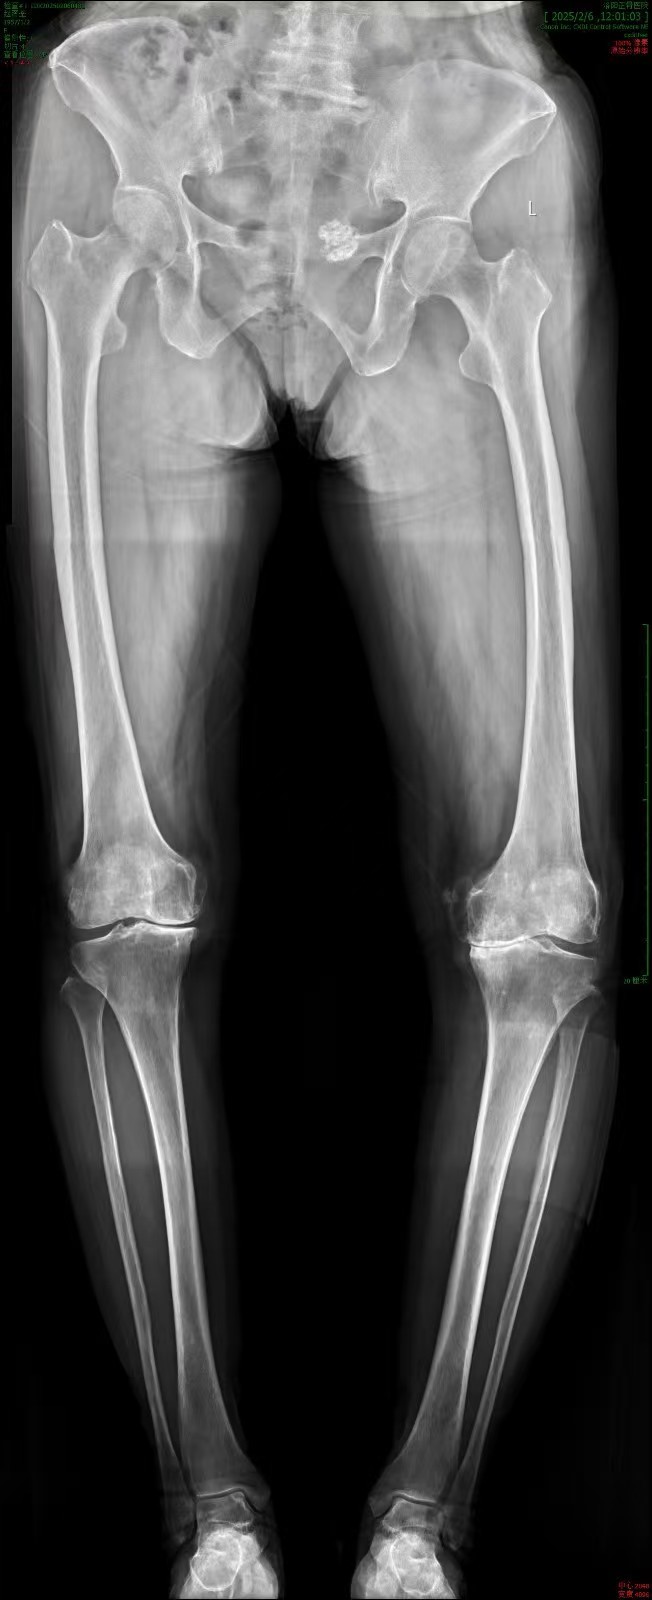

此次接受手术的,是一名62岁男性患者,长期受到膝关节严重病变的折磨,膝关节疼痛难忍,行走困难,日常生活受到极大影响。传统的全膝关节置换手术虽然能够有效治疗该疾病,但由于手术操作的复杂性和患者个体差异,手术效果存在一定的不确定性。谭红略主任团队经过详细评估和充分讨论,决定引入机器人辅助系统,为患者制定个性化的精准手术方案。

手术机器人辅助系统的应用,极大地提升了手术的精准性和安全性。该系统在术前通过对患者的CT影像进行精准分析,能够构建出膝关节的三维立体模型,为医生提供直观、清晰的解剖结构信息。基于这些数据,谭红略主任团队能够精确规划手术方案,确定假体的最佳尺寸、位置和角度,真正实现“量体裁衣”式的个性化治疗。